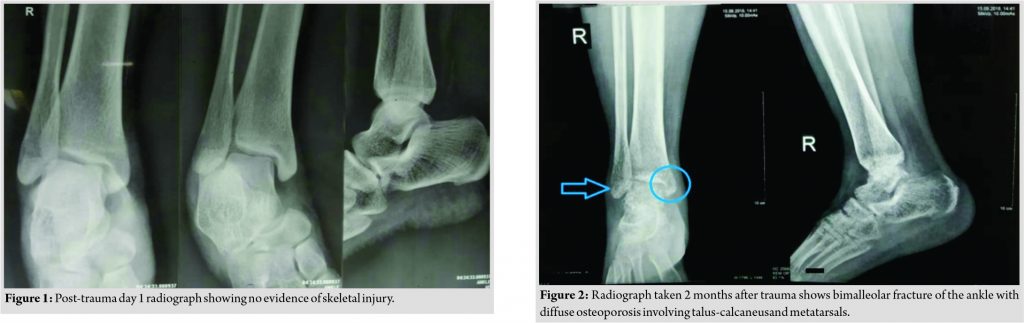

A 30-year-old female presented 2 months after trauma to the right ankle due to a fall from the bike. A radiograph of the ankle demonstrated no evidence of any bony injury (Fig. 1). As per records, there was no evidence of ligament injury based on magnetic resonance imaging evaluation. Consequent to severe pain and swelling patient was treated conservatively and immobilized in below-knee splintage for a period of 8 weeks. She was kept nil weight bearing for the entire duration. After removal of the splintage, the patient continued to have severe pain and swelling and was unable to bear weight. At this point of time, the patient presented to our clinic where follow-up radiographs demonstrated a bimalleolar fracture of the right ankle and diffuse osteoporosis involving talus calcaneum and metatarsals (Fig. 2). After thorough exclusion of other metabolic bone diseases based on various laboratory parameters, the diagnosis of CRPS was made as per Budapest criteria.